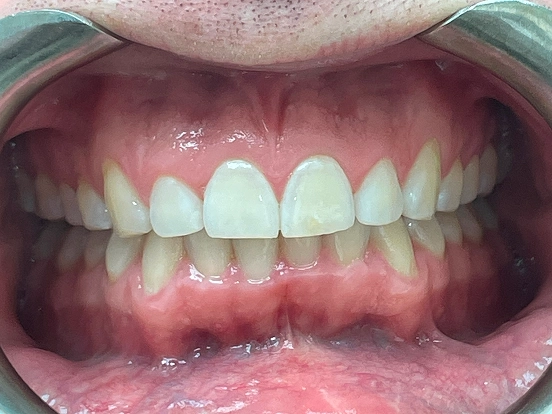

Braces MP

MP’s before and after results highlight the precision of modern braces. The treatment corrected both alignment and bite discrepancies, creating a natural-looking, even smile that enhances overall facial aesthetics and oral health.